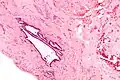

High magnification micrograph of endosalpingiosis, showing the characteristic cystic spaces lined by a simple epithelium with cilia. H&E stain.

It is characterized by cysts with tubal-type epithelium (e.g. ciliated epithelium) surrounded by a fibrous stroma. It is not often associated with hemorrhage.